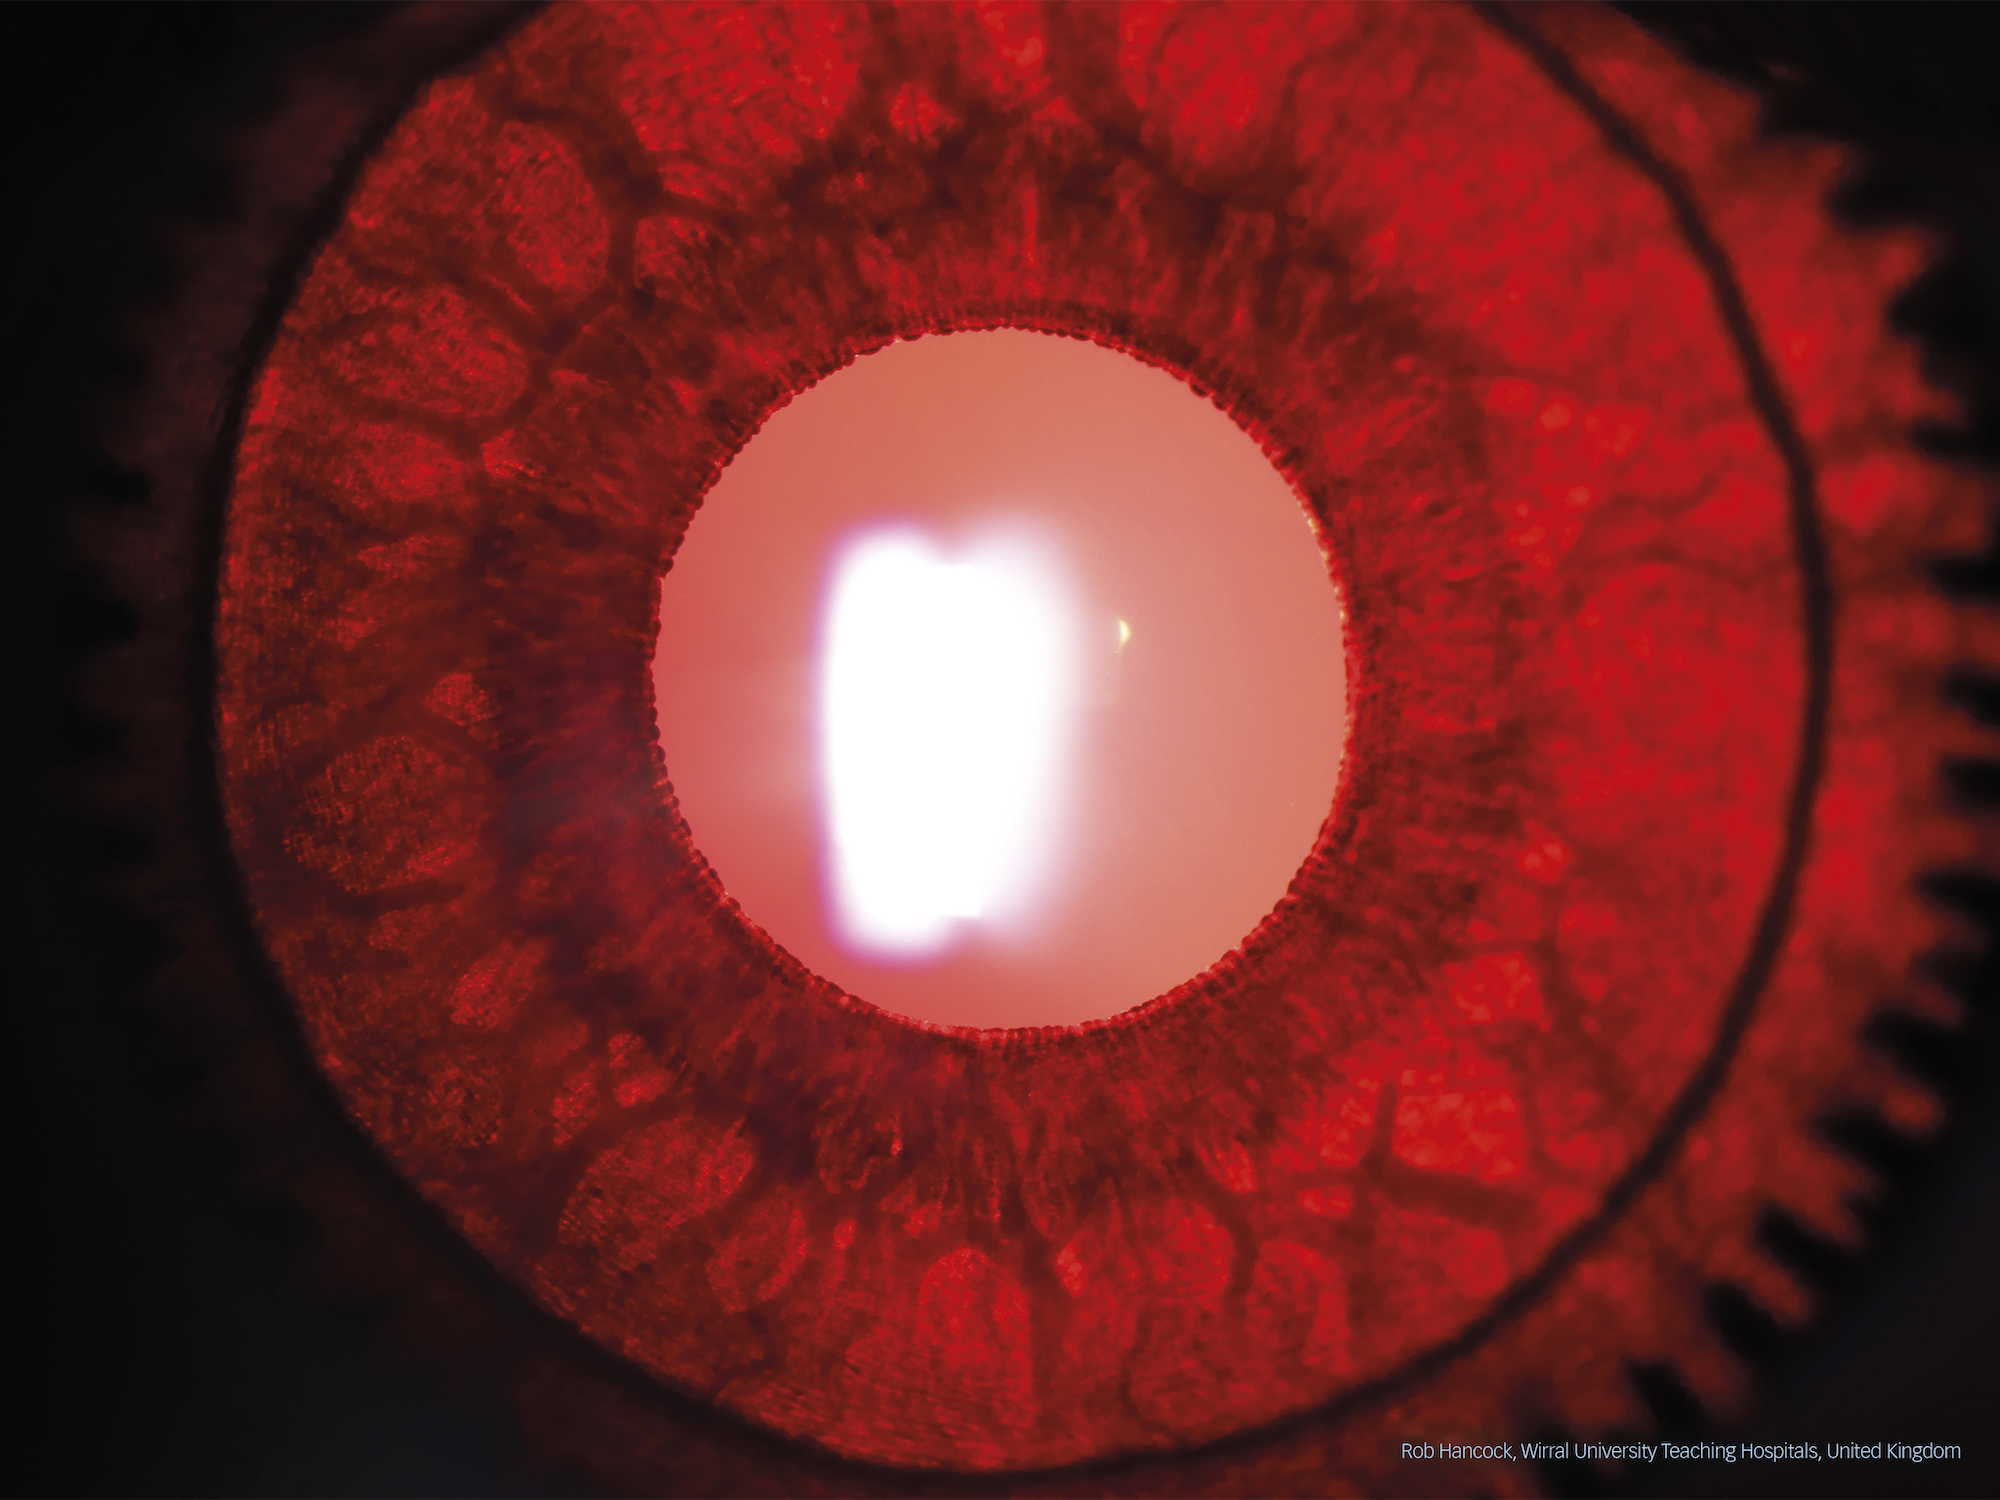

Rob Hancock from Wirral University Teaching Hospital in Wirral, UK, won second prize and received a Nikon Z fc Double Zoom Kit. His image, also taken on a Haag-Streit BX 900 slit lamp, displays a patient with ocular albinism and was captured with an iris transillumination technique. The image was selected by the jury for being “crisp, detail-rich and showing a high level of contrast”.

Ocular albinism by Rob Hancock